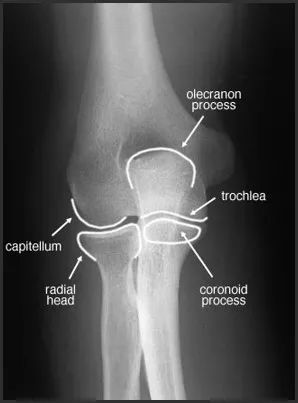

骨折的移位与成角图片

骨折的移位与成角图片,骨折成角移位示意图